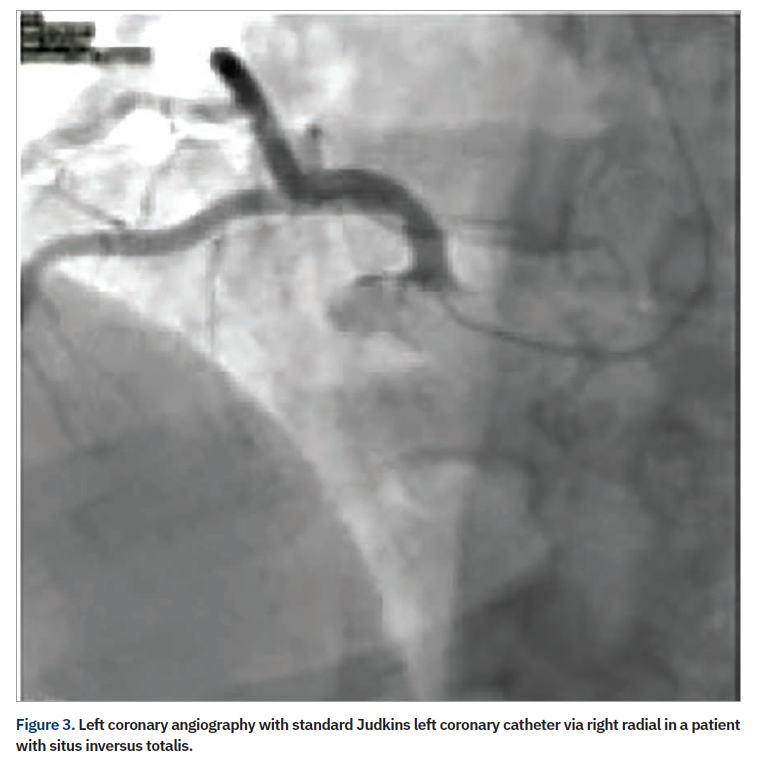

A review of 2100 failed transradial approaches for PCI found age >75 years (P<.001); prior coronary bypass surgery (CABG) (P<.001), and height <5 feet, 5 inches (165 cm) (P=.02) as independent predictors.9 Another study examined 1609 patients and found previous CABG, cardiogenic shock, and female sex as multivariable predictors for transradial failure of PCI (with right radial the default for transradial procedures, except in the case of prior CABG).10 Although a more experienced radial operator will often overcome the challenges of a right radial approach, there are still some patients where the majority of operators favor femoral access, such as patients with history of CABG. In a subgroup of patients (Table 1), access via the left radial artery may allow programs to “stay radial”. The catheter passing via the left arm follows a similar path as the femoral approach, with only one area of resistance in its path, at the left subclavian-aorta junction; conversely, the catheter passing via the right arm has two areas of resistance in its path, at the subclavian-brachiocephalic and the brachiocephalic–aortic junctions (Figure 2).11 An example of the analogy is the ease of right radial in those with situs inversus totalis (Figure 3), where with only one spot of resistance, the typical femoral catheters can be used easily via the right wrist.12